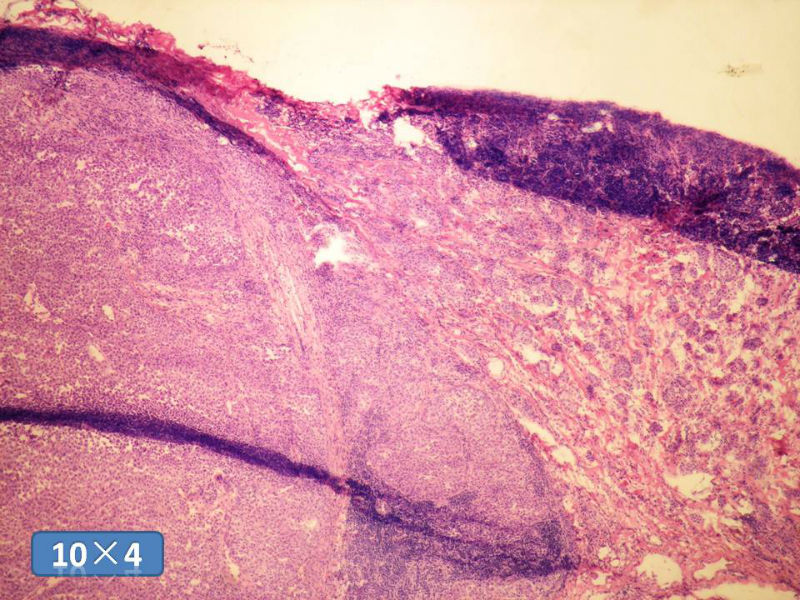

女性,50岁,乳腺肿物,冰冻切片(图1-25)

HE

IDC